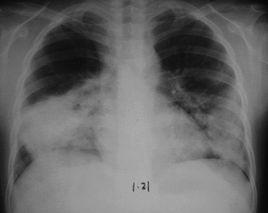

“白肺”病往往病因複雜,來勢兇險,臨床上對於該病的病原學診斷很難。治療該病的關鍵在於尋找病因並及時有效的綜合治療。一位併發症很多的糖尿病患者,2010年11月,在一次感冒後出現呼吸窘迫,經X線檢查顯示兩肺呈白色,被診斷為重症肺炎合併呼吸衰竭,並伴有心臟、腎臟等多個器髒功能衰竭,生命危在旦夕。明確診療,立即採取氣管切開、採用保護性肺機械通氣等措施,改善患者氧氣供應。在此基礎上,治療組根據臨床經驗和實驗數據,選擇對患者最適宜敏感的抗微生物製劑治療,終於挽救了患者的生命。

對於何時用哪種藥物治療,以及何時插管、何時吸痰、何時給氧等都有非常多的講究。同時,還需要密切觀察患者尿量、尿色、排便、體重等變化。對於兒童和老人治療難度和風險則更大。患者慢性支氣管炎、肺氣腫多年,2010年12月在一次感冒後,通過治療出現休克性血壓,當即被送到急診科。初診後發現其嚴重呼吸衰竭,繼而立即給予氣管插管。床旁照片雙肺呈白色,診斷為重症肺炎、敗血症、感染性休克,病情及其危重。由於患者平時營養狀態不佳,加之病情危重複雜、年齡偏大、多器髒衰竭,在經口氣管插管治療1周后,一方面用強有力的抗生素治療嚴重細菌感染,另一方面改善血液循環、調整機體微環境、加強營養支持。